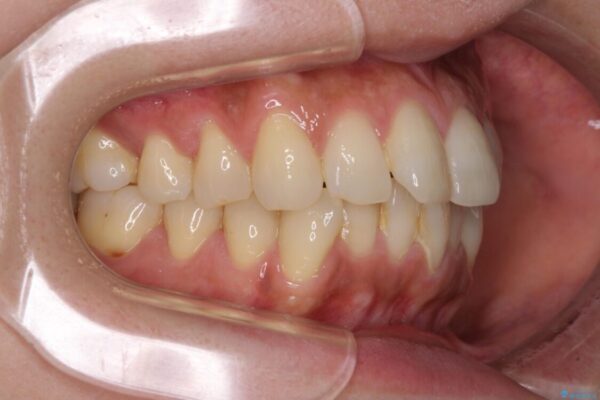

治療後

• インビザラインによる矯正治療と奥歯のインプラント治療 治療後画像

治療後について

歯の傾斜が改善され、インプラントによるクラウンが装着されたことで、物が挟まることもなくなりました。